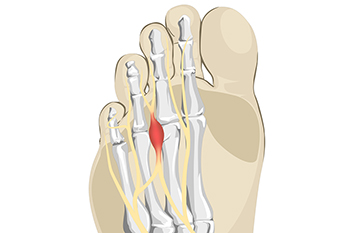

Constricting Shoes May Cause Morton’s Neuroma

Morton’s neuroma is one of the most painful foot conditions that can develop. The pain is felt between the third and fourth toes and results due to an inflamed nerve. If the arch is weak the nerve can become compressed, causing the tissues to thicken. This can happen from wearing shoes that do not have enough room for the toes to move freely in, therefore the nerve becomes irritated. A numbness or tingling sensation can often be felt with this condition and walking may become difficult. Morton’s neuroma may also gradually develop from extreme overpronation which is the foot continuously rolling inward while walking. This may cause the bones in the front of the foot to compress the nerve. Effective treatment generally begins with frequently resting the foot and some patients choose to insert a cushioned pad into the shoe. If you have developed Morton’s neuroma, please confer with a podiatrist who can effectively treat this condition while offering you pain relief options.

Morton’s neuroma is a very uncomfortable condition to live with. If you think you have Morton’s neuroma, contact one of our podiatrists of Brondon Foot and Ankle. Our doctors will attend to all of your foot care needs and answer any of your related questions.

Morton’s Neuroma

Morton's neuroma is a painful foot condition that commonly affects the areas between the second and third or third and fourth toe, although other areas of the foot are also susceptible. Morton’s neuroma is caused by an inflamed nerve in the foot that is being squeezed and aggravated by surrounding bones.

What Increases the Chances of Having Morton’s Neuroma?

- Ill-fitting high heels or shoes that add pressure to the toe or foot

- Jogging, running or any sport that involves constant impact to the foot

- Flat feet, bunions, and any other foot deformities

Morton’s neuroma is a very treatable condition. Orthotics and shoe inserts can often be used to alleviate the pain on the forefront of the feet. In more severe cases, corticosteroids can also be prescribed. In order to figure out the best treatment for your neuroma, it’s recommended to seek the care of a podiatrist who can diagnose your condition and provide different treatment options.

If you have any questions, please feel free to contact our office located in Centerville, OH . We offer the newest diagnostic and treatment technologies for all your foot care needs.

Morton's Neuroma

Morton's Neuroma, also called Intermetatarsal Neuroma or Plantar Neuroma, is a condition that affects the nerves of the feet, usually the area between the third and fourth toe. Neuroma refers to a benign growth that can occur in different parts of the body. Morton's Neuroma strictly affects the feet. This condition causes the tissue around the nerves that lead to the toes becoming thick, causing pain in the ball of the foot.

This condition can be caused by injury, pressure or irritation. Normally no lump will be felt, but instead burning pain in the ball of the foot will be experienced. Numbness and tingling may also occur. With the onset of this condition, a person may feel pain when tight or narrow shoes are worn. As the condition worsens, the pain may persist for days, or even weeks.

Persistent foot pain should always be a concern. The foot should be examined by a podiatrist if pain persists longer than a few days with no relief from changing shoes. The earlier the foot is examined and treated, the less chance there will be for surgical treatment.

There are some factors that can play a role in the development of Morton's Neuroma. These include wearing ill-fitting shoes that cause pressure to the toes, such as high heels. Also, high impact exercise may contribute to the cause of this condition. Morton’s Neuroma may also develop if the foot sustains an injury. Another cause includes walking abnormally due to bunions or flat feet. This causes excessive pressure and irritates the tissue. At times, people are affected for no determinable reason.

Podiatrists can alleviate the effects of this condition using a treatment plan to help decrease the pain and heal the foot tissue. Depending upon the severity of the Morton's Neuroma, the treatment plan can vary. For cases that are mild to moderate, treatments may include applying padding to the arch to relieve pressure from the nerve and reduce compression while walking. Ice packs can also help reduce swelling. The podiatrist may also create a custom orthotic device to support the foot and reduce compression and pressure on the affected nerve. The doctor will probably advise against partaking in activities that cause constant pressure on the affected area. They may provide wider shoes to ease the pressure from the toes. If these treatments do not relieve the symptoms of this condition, the doctor may use injection therapy.

Surgical treatment may be recommended by the podiatrist if all other treatments fail to provide relief. Normally, the podiatric surgeon will decide on either a surgical procedure that involves removal of the affected nerve or will choose surgery to release the nerve. After examination, the surgeon will decide on the best approach to treat the problem.

Recovery varies according to the type of surgical procedure. The patient will also be instructed on the best shoe wear to prevent the return of this condition, along with changes to workout routines, if this was a cause. Preventative measures are important in ensuring the condition does not return.